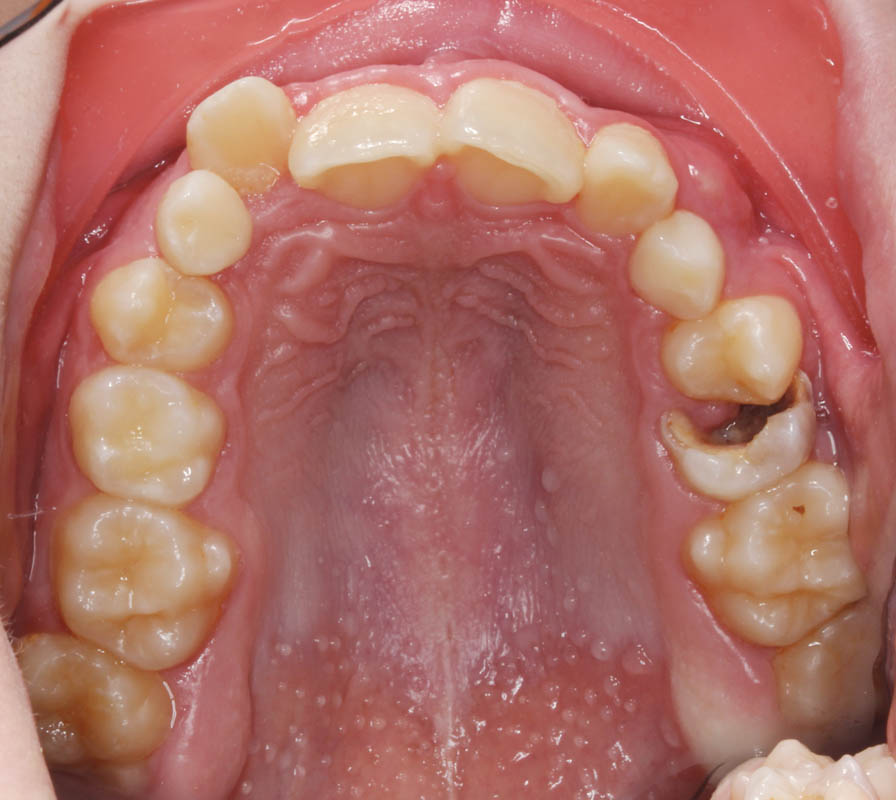

La frecuencia relativa de inclusión varía de unos dientes a otros (Tabla 1), siendo los terceros molares inferiores los dientes incluidos con mayor frecuencia, seguidos de los caninos superiores (2).